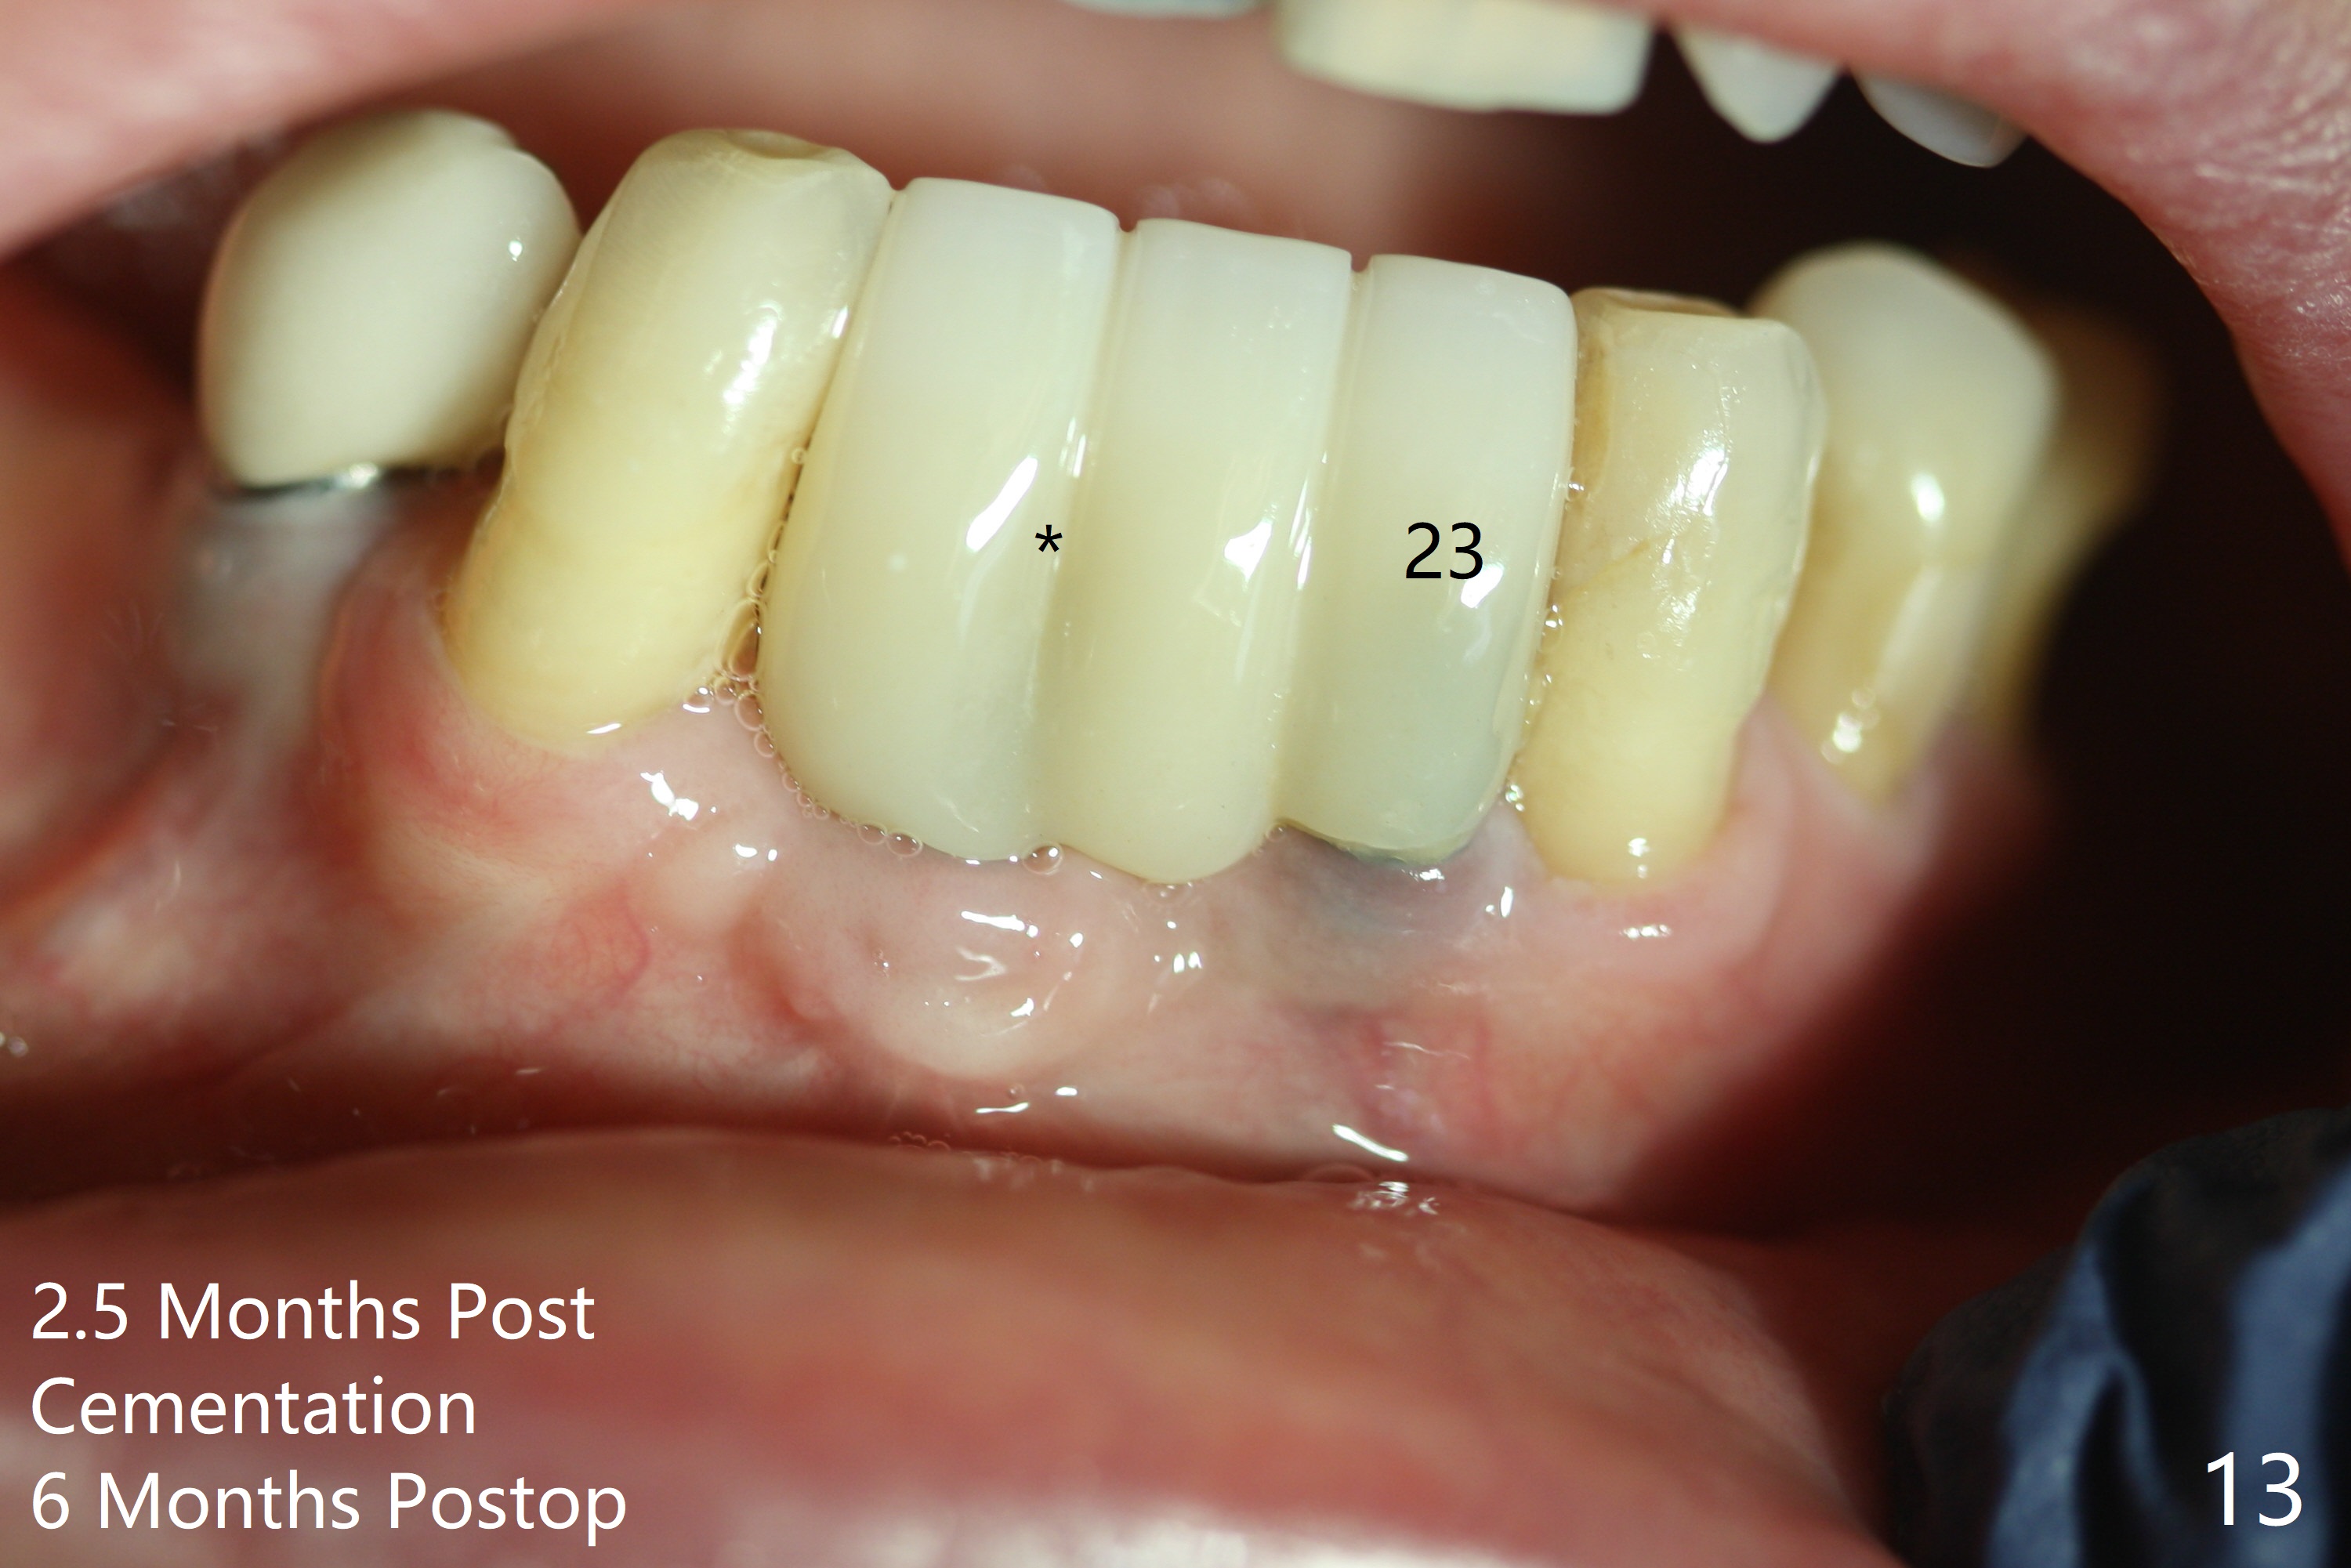

The wound at #25 seems to heal 1 month postop; after prep (Fig.10,11), a provisional FPD is fabricated. Impression is taken for surgical guides of UL and LL implants. The patient requests early final restoration (Fig.12). The small implant placed lingually (Fig.12 *, 2 mm) is associated with the pleasing gingiva in color, as compared to the 3 mm one at #23 with the metal shaded gingiva.